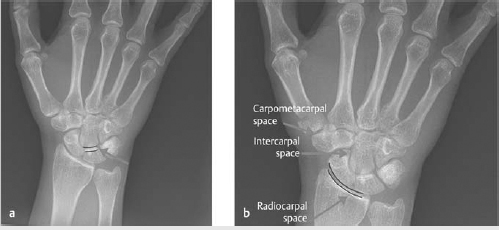

III. Joint Spaces: Parallelism and Symmetry

The joint spaces of the wrist normally have a width of 2 mm or less (► Fig. 3.3).

Radiocarpal joint is slightly wider than the rest, carpometacarpal joints are slightly narrower.

The capitolunate joint is used as reference to which other joint spaces can be compared.